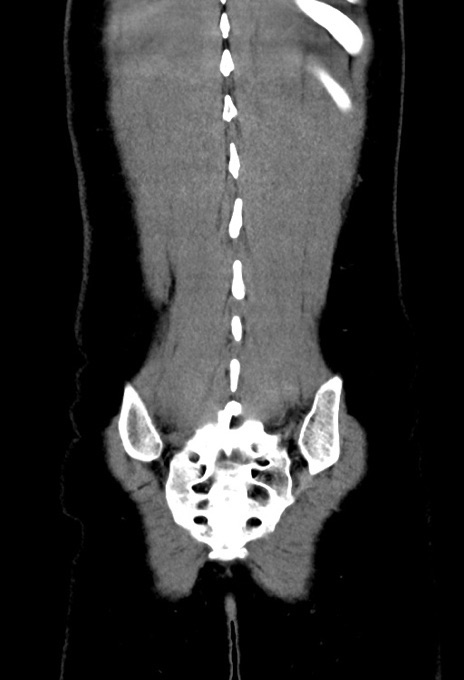

症例17(冠状断像)

【症例】20歳代女性

【主訴】嘔吐、下腹部痛

【現病歴】昨日夕食後に嘔吐し下腹部痛が出現。本日になっても嘔吐持続し改善しないため来院。

【身体所見】意識清明、BT 37.2℃、BP 108/67mmHg、腹部:平坦、やや硬、下腹部正中から右にかけて圧痛あり、反跳痛軽度あり、tapping pain(+)。

【データ】WBC 13600、CRP 14.94